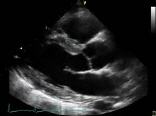

Die Echokardiographie ist eine Ultraschall-Untersuchung des Herzens. Sie ist das wichtigste Untersuchungsverfahren für die Beurteilung der Herzstruktur und

Herzfunktion und gehört beispielsweise bei Verdacht auf Herzinfarkt, Herzinsuffizienz oder Myokarditis zu den Standarduntersuchungen. die Echokardiographie ist eine sanfte Untersuchung ohne Strahlenbelastung.

Bei der transthorakalen Echokardiographie wird der Ultraschallkopf außen auf die vordere Brustwand gelegt, während Sie sich auf einer Untersuchungsliege befinden. Der Arzt richtet den Ultraschallkopf nun gegen die verschiedenen Teile des Herzens aus, um ein möglichst genaues Bild aller Herzstrukturen zu erhalten, die auf einem Bildschirm angezeigt werden.